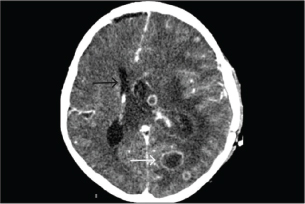

KOH examination of the abscess material demonstrated septate hyphae. Histopathological analysis of the brain abscess from the right frontal lobe revealed uniform, dichotomously branching septate hyphae with acute-angle branching infiltrating the vascular wall and surrounding brain parenchyma (Fig. 2). CSF analysis revealed hypoglycorrhachia, elevated protein, and neutrophilic pleocytosis (Table 1). Cryptococcal antigen testing was negative. There was no radiologic evidence of disseminated aspergillosis involving the lungs or paranasal sinuses. Extensive microbiological investigations for aerobic and anaerobic bacteria, Mycobacterium tuberculosis, Nocardia spp., herpes simplex virus, cytomegalovirus, and Toxoplasma gondii were negative. Serum galactomannan testing showed 0.42; CSF galactomannan and β-D-glucan assays were not performed. These findings supported a diagnosis of multiple cerebral abscesses caused by aspergillosis without evidence of extracranial dissemination.

Fig. 2. Brain abscess, Hematoxylin and eosin (H&E) stain, 40×: on day 23 of admission, Fungal hyphae typically branch at acute angles in the necrotic area (black arrow).